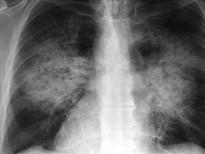

问题 患者输液过程中突发胸闷,气急,咳痰,胸部正侧位片如图,最可能的诊断为 ( )

选项 A.硅沉着病合并感染 B.中央型肺水肿 C.真菌感染 D.间质性肺水肿 E.腺病毒肺炎

答案 B